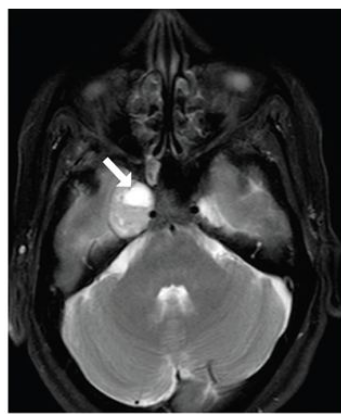

圖:海綿竇血管瘤,T2高信號(hào),累及左側(cè)Meckel腔